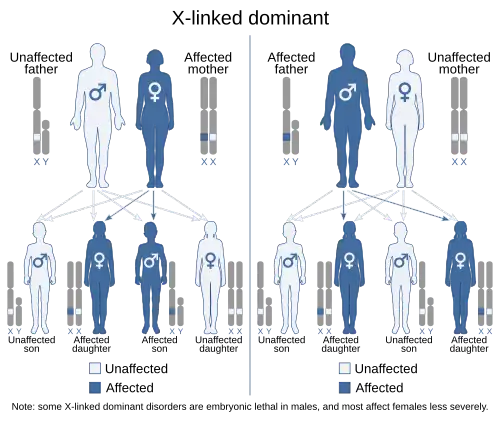

| This condition is inherited in an X-linked dominant manner. However, unlike most X-linked conditions, it is more severe in females, due to cell–cell interaction mechanisms involving the responsible gene (EFNB1) when it is present in only some cells (mosaic). | |

Paradoxical to other X-linked conditions, with CFND the females are more severely affected than males.[3] This is due to the process of X-inactivation in females, where at random either the maternal or paternal X-chromosome is inactivated in a cell.[3][10] Due to this process, the body’s tissues contain either cells with normal EFNB1 or the mutated EFNB1. This is called a mosaic pattern.[3][10][11] This mosaic pattern of cells 'interferes' with the functionality of the cell-cell interactions, as a result causing the severe physical malformations in females.[11][12]

As with all X-linked conditions CFND has a preset chance of being passed down from parents to their offspring. Females have two X-chromosomes and males have one X-chromosome. When a mother is a carrier of CFND, there is a 50% chance of her passing down the X-chromosome containing the mutated EFNB1 gene to her offspring, regardless if the child is a boy or girl. If the father is a carrier there is a 100% chance of him passing down his X-chromosome with the EFNB1 mutation to a daughter, and 0% chance of him passing it down to a son.[3]